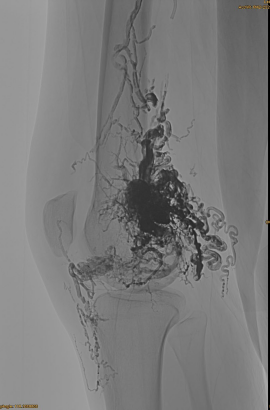

Gwybodaeth sylfaenol y claf: benyw, 36 oed; AVM Pelvis, clun, pen -glin, OSG chwith, lluosog cyn -- embolizations.

Cynhyrchion a ddefnyddir: 3pcs lava-34,14pcs lava-18.

DSA cychwynnol:

Canlyniad terfynol:

Prin unrhyw all -lif gwythiennol:

Cyfnod hwyr, EMBO arall yn angenrheidiol, ond yn llawer gwell: